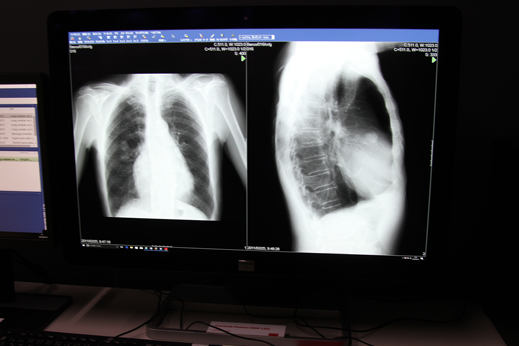

バルコは、診断用画像表示ソリューションと外科用画像表示ソリューションとに分け、来場者にそれぞれのソリューションで展示を行った。暗室内でのモニター展示や、手術室を再現した大型モニターの展示は例年の定番となっているが、今回も来場者の興味を引き付けるブース仕様となっていた。